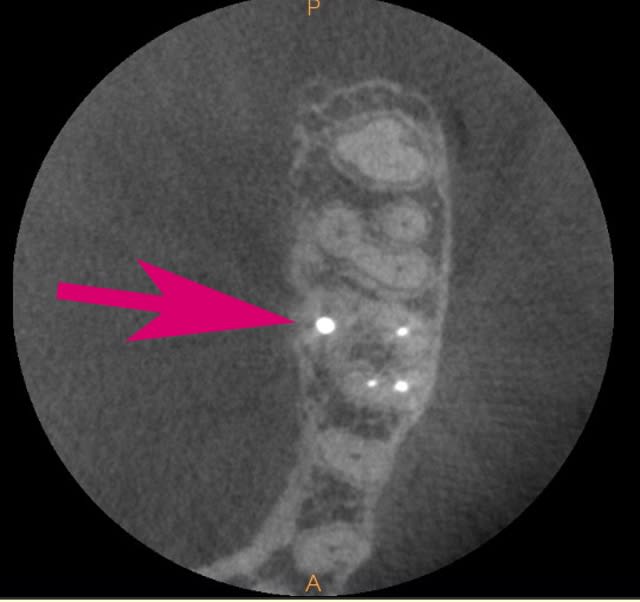

Il ya encore un souci d'artéfact important quand il y a un fort contraste exemple obturation endo très dense ou tenon métallique ((flèche sur image jointe).